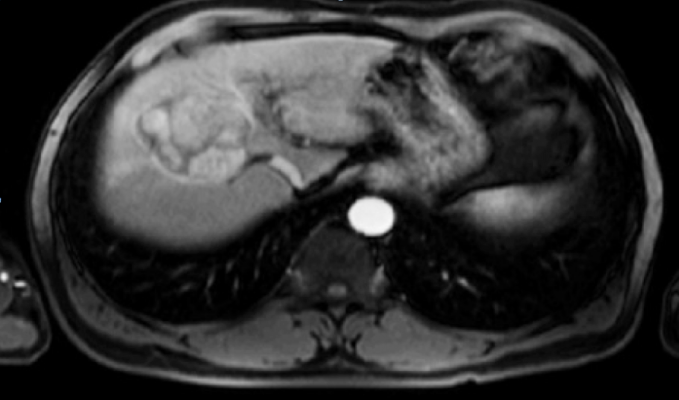

iBiopsy is Median's investigational platform designed to acquire, index and analyze imaging phenomics, decoding disease biomarkers from standard medical images. The system provides insights into the development of novel therapies and individualized treatment strategies. The first application of iBiopsy is for the assessment of nonalcoholic steatohepatitis (NASH), a liver disease which is dramatically increasing in prevalence in all parts of the world.

iBiopsy is also the backbone of Median's development efforts and combines the latest advances in artificial intelligence (AI) and big data predictive analytics to harness the power of imaging phenomics.